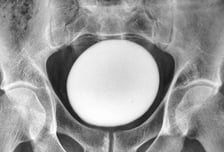

"뱃속에 타조알이?"…35세 남성 방광서 발견된 거대 결석 '충격'

이란에 거주하는 30대 남성의 방광에서 마치 타조알처럼 보이는 커다란 결석이 발견됐다. 7일(현지시간) 과학 매체 라이브사이언스는 이란의 35세 남성이 방광의 불편함을 호소하며 비뇨기과를 찾았다가 의료진들을 놀라게 했다고 보도했다. 해당 남성은 방광 부위에 불편감을 느껴 병원을 방문했다. 소변을 보는 데는 문제가 없었고 과거 수술이나 질병 이력도 없었다. 잦은 배뇨나 소변볼 때 타는 듯한 느낌 같은 요로감염 증상도 없었다. 의사들은 환자의 복부를 진찰하던 중 치골 위에서 크고 매끄러우며 단단한 덩어리가 만져져 초음파 검사를 실시했다. 그 결과 환자의 방광 안에 지름 11㎝의 커다란 결석이 있음을 확인했다. 방광결석은 방광 안에 돌과 같은 단단한 결정이 형성된 상태를 말한다. 전립선 비대증이나 요도협착 등 소변이 방광에서 완전히 배출되지 못하는 상황에서 소변 속 미네랄 농도가 높아져 결석이 형성될 수 있다. 해당 남성은 방광 절개술을 받고 결석을 제거했다. 제거된 결석은 길이 13㎝, 너비 10㎝, 높이 8㎝로 무게만 약 826g에 달한 것으로 알려졌다.